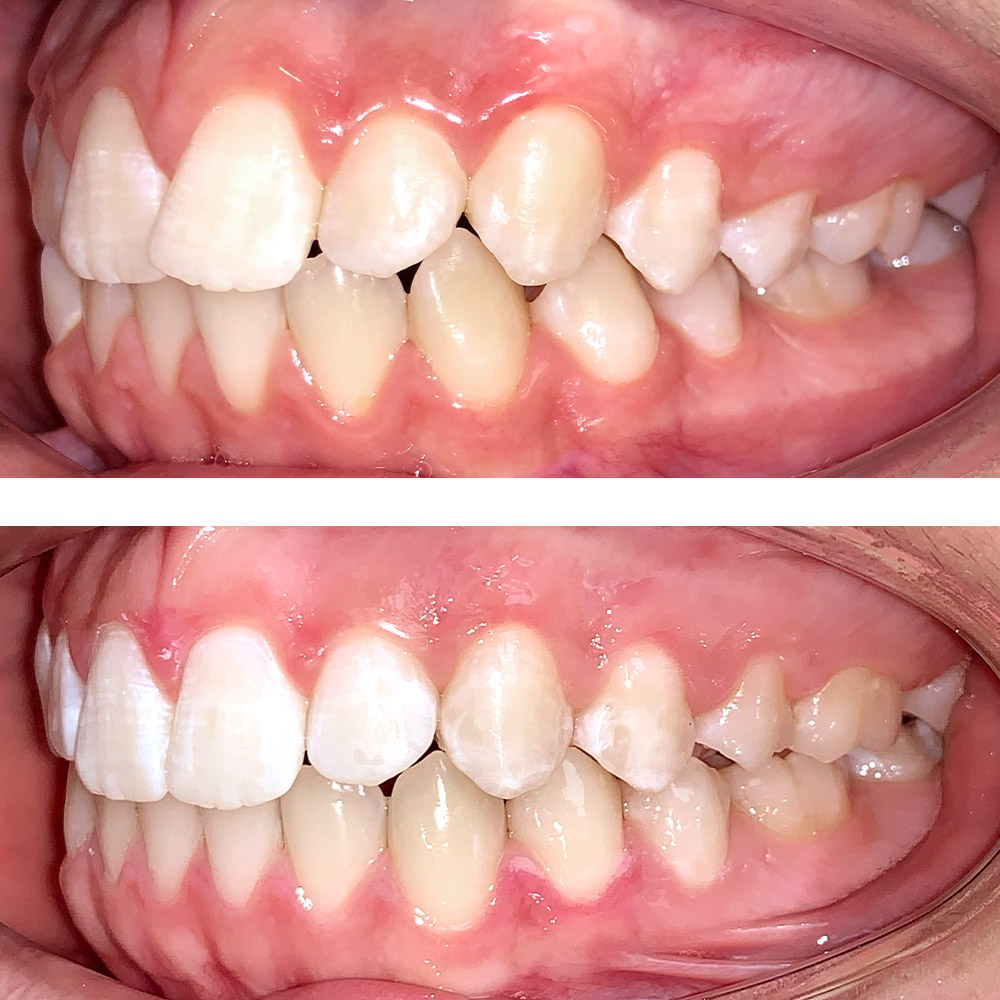

Кейс 16

Акинфиева

Количество кап ВЧ 20

Количество кап НЧ 20

ДО

ПОСЛЕ